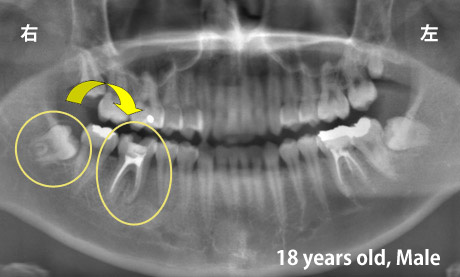

歯の移植

適切な条件がそろえば、歯の移植が可能です。歯の移植とは、治療することができない歯を抜いて、その場所へ本人の親知らずなどの歯を移す治療です。例えば、下のパノラマエックス線写真は18歳の男子です。右下の第一大臼歯が割れて痛みを伴って来院されました。この歯の保存できないと判断して、その歯を抜歯し,後ろにあるまだ生えていない親知らずをそこへ移植しました。移植の適切な条件とは、患者さん年齢が概ね40歳以下であること、口腔内に適切なドナー歯(主に親知らず)があること、移植歯(ドナー歯)と移植部位(受容側)の大きさが適合すること、などです。